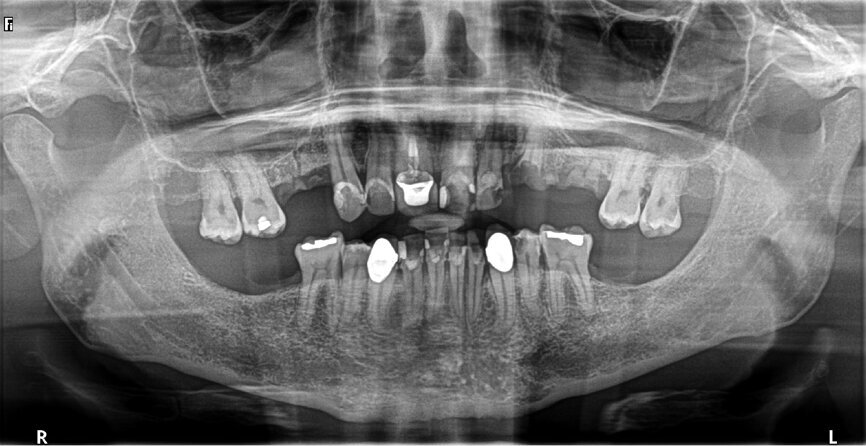

A patient presented to my practice for a consultation wanting to restore his dentition to proper form and function (Fig. 1). He complained of generalised discomfort due to the gross caries and periodontal disease that was readily apparent (Figs. 2 & 3). There were several teeth in both arches that had so much extensive decay that only the root tips were apparent upon clinical examination. Also, there was hyper-eruption in certain areas of his posterior dentition, as well as a deep impinging bite in the anterior.

Fig. 5: Pre-op panoramic view.

A CBCT scan and panoramic radiograph using the CS 8100 3D (Carestream Dental; Figs. 4 & 5) was taken to accurately capture the information needed to properly plan treatment for this case to ensure the most ideal outcome, especially since the patient had discussed his frustration with previous treatment that did not last very long or address his primary needs or requests. Using CS 3D Imaging Software (Carestream Dental), dental implants were virtually planned in key positions in both arches (Fig. 6).